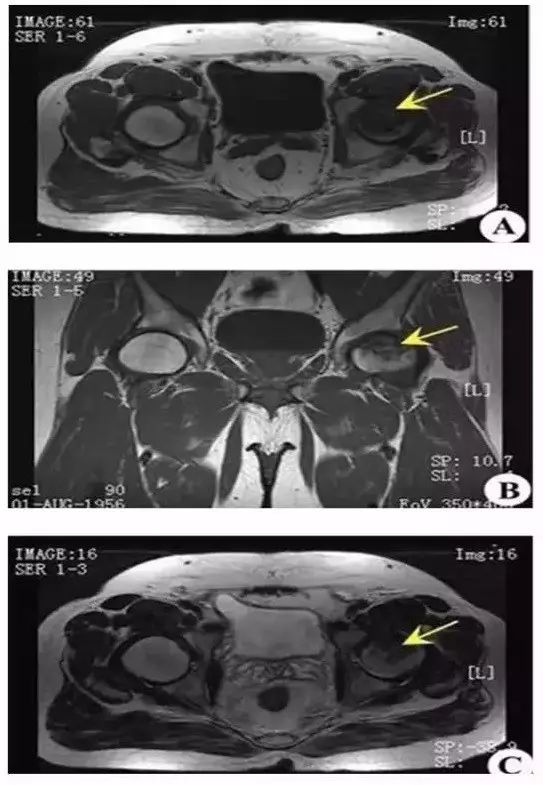

股骨头坏死的 MRI 表现

MRI 敏感性优于骨核素扫描和 CT 及 X 线检查。这是因为股骨头发生坏死后,修复组织不断伸入坏死区上方骨髓的变化早于骨质变化,MRI可以在骨质塌陷及修复以前反映出骨髓细胞的变化。所以, MRI 应作为早期检查诊断骨坏死的主要手段。

I 期 股骨头不变形,关节间隙正常,X 线平片、CT多不能显示明显的骨质病变,称 X 线前期。T1 加权股骨头负重区(根据关节软骨结构和功能的特点,将股骨头软骨面分为三个部份,外上方与髋臼软骨面相差的压力负重区、压力负重区内侧的非压力负重区和外侧周围的非压力负重区)显示线样低信号。T2 加权呈高信号病理特征,是骨和骨髓的坏死无修复,以骨髓水肿、骨细胞坏死、骨陷窝空虚为主要改变。

Ⅱ 期 股骨头不变形,关节间隙正常。T1 加权为新月形边界清楚的不均匀信号,T2 加权显中等稍高信号,周围不均匀稍低信号环绕,呈典型的双线征,位置基本与CT的条状骨硬化一致。病理上为病灶中心大量不规则的细胞碎片坏死,周边纤维化,新骨形成和肉芽组织增生。

上图为II期

Ⅲ 期 股骨头变形,软骨下骨折、塌陷、新月体形成。T1 加权呈带状低信号,T2 加权示中等或高信号,为关节积液进入软骨下骨折线的裂隙。新月形坏死骨发生应力性软骨下骨折、塌陷并与关节软骨分离。由于纤维组织长入形成致密的无血管墙,使修复被阻挡,进入坏死骨的修复受限。

上图为Ⅲ期